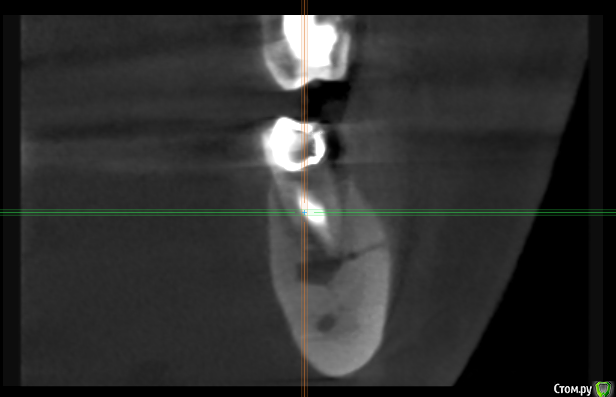

kramer Опубликовано 2 мая, 2018 Поделиться Опубликовано 2 мая, 2018 Коллеги! Помогите, пожалуйста, советом. Пациент обратился с жалобами на зуб 36, характерными для периодонтита (дискомфорт при накусывании, периодические обострения и т.д.). Зубы 35,34 интактные. Сделал КТ, вот что там: Синус-тракт в области 36: Область 35: Мезиально очаг поражения достигает апекса 34 и, видимо, уже частично разрушил компактную пластинку: Если это обычный периодонтит, то 1) почему такие странные очертания очага (или не странные?) 2) с 36 все понятно, но как могли быть поражены 35 и 34? Ссылка на комментарий

TIGER Опубликовано 3 мая, 2018 Поделиться Опубликовано 3 мая, 2018 Коллеги! Помогите, пожалуйста, советом. Пациент обратился с жалобами на зуб 36, характерными для периодонтита (дискомфорт при накусывании, периодические обострения и т.д.). Зубы 35,34 интактные. Сделал КТ, вот что там: раф1.png Синус-тракт в области 36:раф2.png Область 35:раф3.png Мезиально очаг поражения достигает апекса 34 и, видимо, уже частично разрушил компактную пластинку:раф4.png Если это обычный периодонтит, то 1) почему такие странные очертания очага (или не странные?) 2) с 36 все понятно, но как могли быть поражены 35 и 34? Гранулирующий периодонтит от 6 зуба.... Ссылка на комментарий